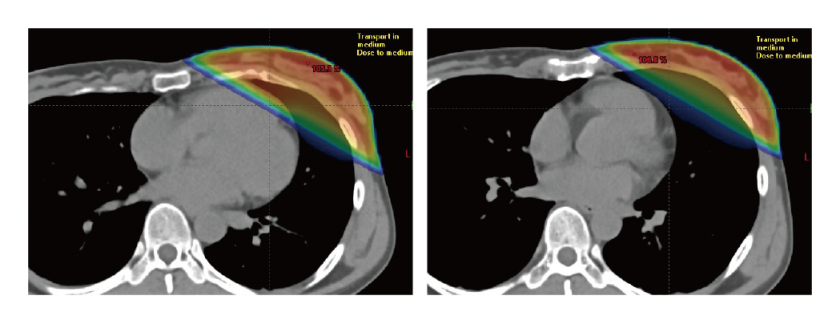

DIBH(深吸気息止め)

左乳がんへの放射線治療において、心臓への放射線被ばくを減らし心臓障害のリスクを下げる方法。当院では昨年から、左乳がんの乳房温存術後照射に導入しています。大きく息を吸うことで肺をふくらませ、心臓と患部が十分に離れた状態を維持している間に照射します。